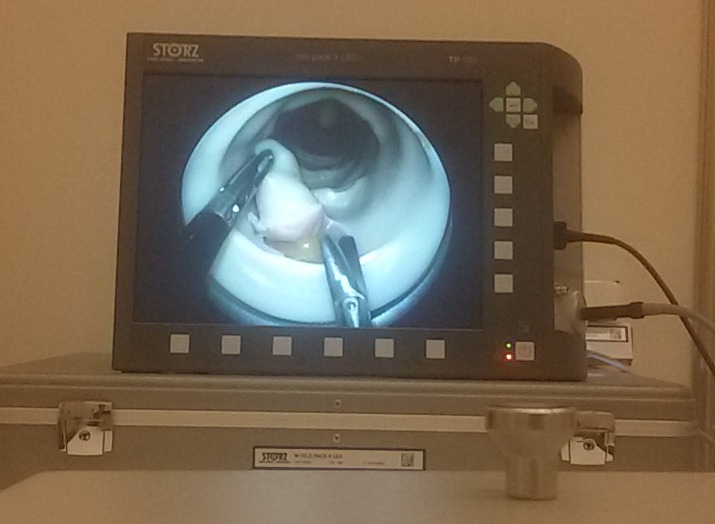

Також була нагода взяти участь в курсі Transanal Endoscopic Microsurgery (TEM) та Transanal Endoscopic Operation (TEO).

Ментором курсу був один з лідерів цього виду хірургії Alberto Alezzo з Італії. Обговорили анатомію, можливі підходи і відпрацювали навички на сучасних хірургічних симуляторах Karl Storz.

Корисним був досвід виконувати операції, коли мало простору для маніпуляції інструментами, а потрібно не лише видалити пухлину, але і ліквідувати дефект.